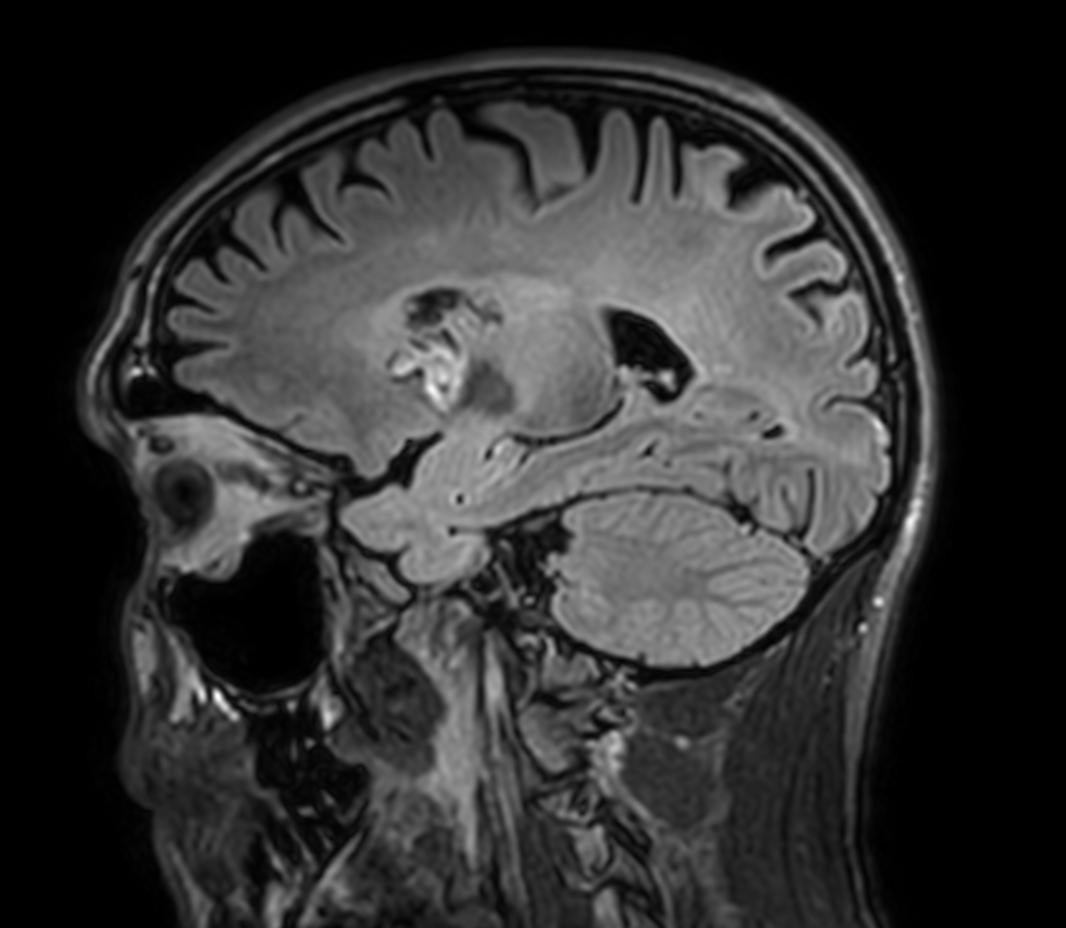

3D VIEW - T1w Black Blood